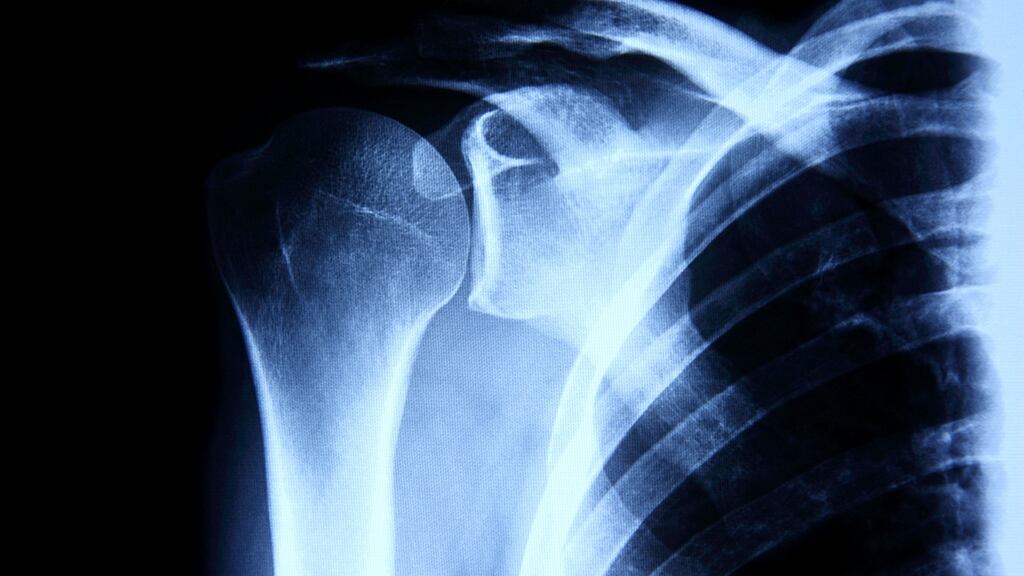

The target market is patients who have suffered high-impact fractures – such as crash victims – and those who have bone damage after the removal of tumours. It can also be used to improve bone structure for people suffering with osteoporosis and even in strengthening the bone foundations of tooth implants.

SurgaColl is also submitting an EU application for another product, ChondroColl – which will address cartilage and bone injury in knee joints – this month.